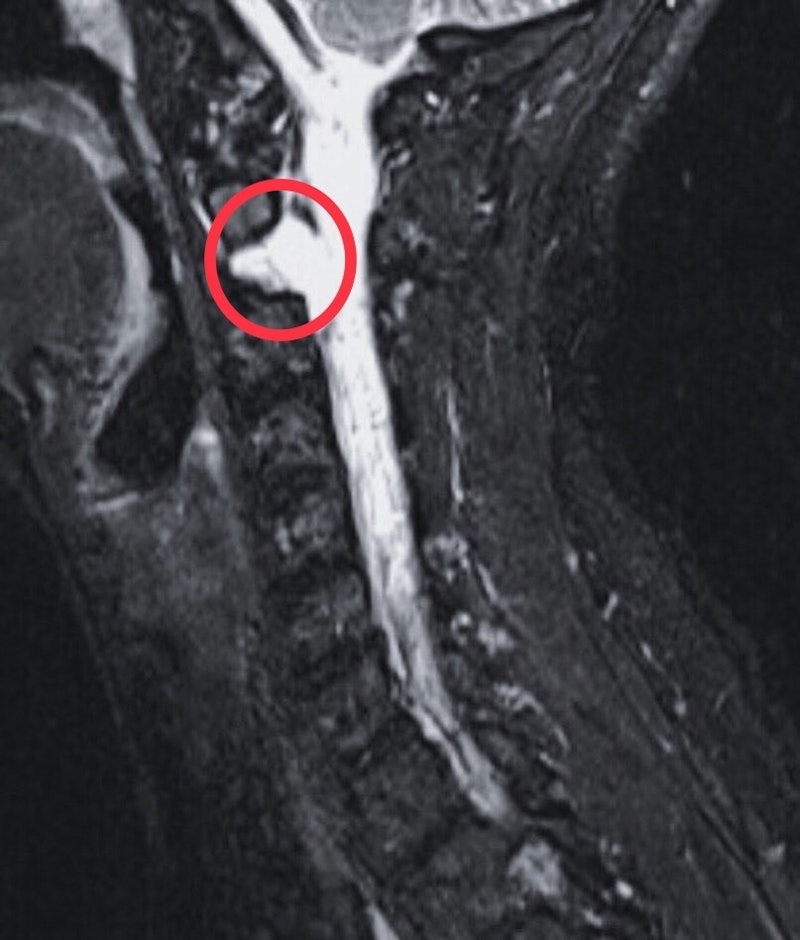

Her MRI revealed a cyst on a vertebra, though neurosurgeons could not prove it was the source. But without any other plausible answers, the cyst became the leading theory—though surgeons would not remove it due to its risky location beside the vertebra-basiliar artery and brain stem.